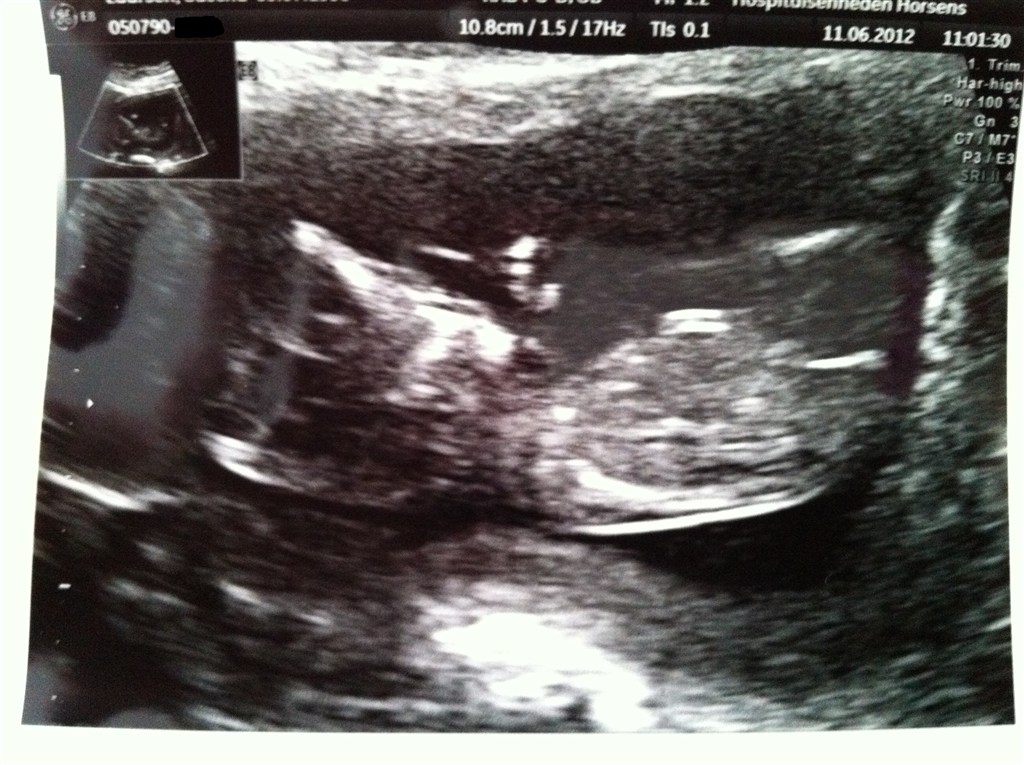

Billedspam af Nakkefoldsscanning i dag den 11.06.2012.

Har været til nakkefoldsscanning i dag og det var godt nok ubeskrivelig den oplevelse, kunne ligge der i flere timer, hvis jeg fik lov hehe. Vores guldklump er alledere 10 cm

Vedhæftede fotos (klik for at se i fuld størrelse)